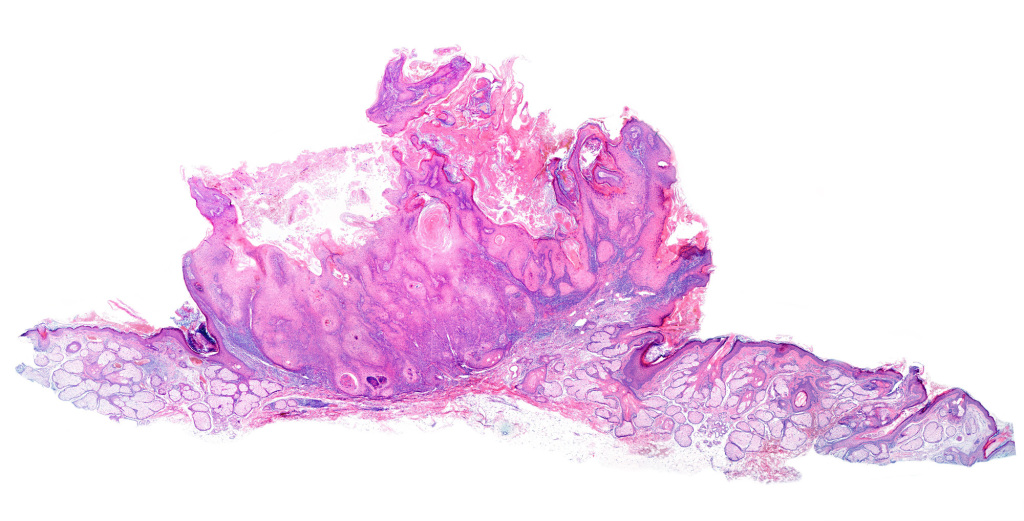

Our medical studies confirmed our interest in histology.